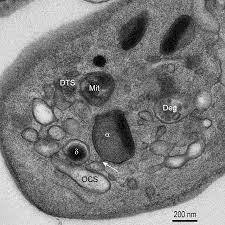

α granules: Low electron density, most abundant. Contains PAF4 (heparin neutralizer) and platelet mitogenic factors (such as PDGF) that stimulate endothelial, smooth muscle, and fibroblast proliferation.

γ granules: Large, less dense than delta (dense) granules. Contain cathepsin, acid phosphatase, and a few beta glucosidases.

δ ganules: The delta stands for dense. Electron dense with a “bull’s eye” appearance. Contain serotonin, calcium, ATP, and ADP.

Peroxisomes: Much smaller than the rest. Contain catalase.